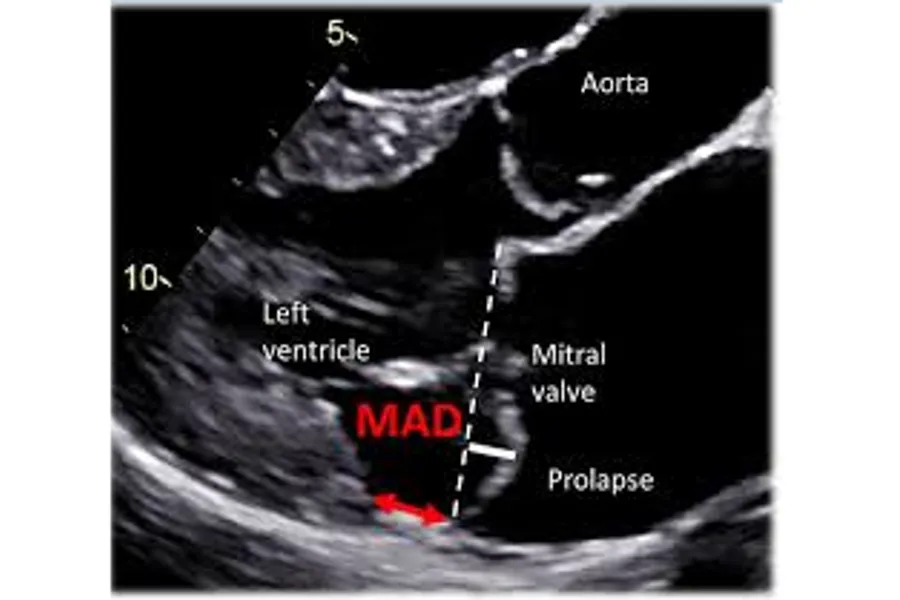

Mitral annular disjunction is a gap between the mitral ring and the ventricular myocardium, and is associated with mitral valve prolapse. A minority of these patients experience life-threatening ventricular arrhythmias, but the incidence of such arrhythmias is largely unknown. Additionally, estimating arrhythmic risk in a clinical setting is challenging and imprecise. The aim of the project was to assess the incidence and explore possible risk markers of ventricular arrhythmias in patients with mitral annular disjunction, with the overall aim to improve risk stratification and follow-up of these patients.

Credit: Lars Dejgaard and Kristina Haugaa, Hjerteforum 2019.